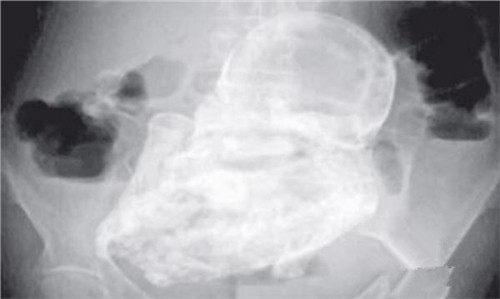

导致胎儿死胎的睡姿图片分享:除趴着睡这三种也要重视!

女性怀孕之后有很多需要注意的地方,除了要按时产检,还需要健康饮食、合理睡眠等,这些都关乎宝宝在孕妇体内的发育情况。大多数孕妇在清醒的时候都会格外注意自己的行为习..